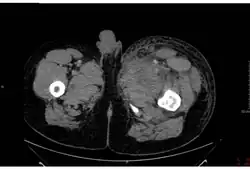

Despite signing the 1972 agreement to end bioweapon production, the government of the Soviet Union had an active bioweapons program that included the production of hundreds of tons of anthrax after this period. On 2 April 1979, some of the over one million people living in Sverdlovsk (now called Ekaterinburg, Russia), about 1,370 kilometres (850 mi) east of Moscow, were exposed to an accidental release of anthrax from a biological weapons complex located near there. At least 94 people were infected, of whom at least 68 died. One victim died four days after the release, 10 over an eight-day period at the peak of the deaths, and the last six weeks later. Extensive cleanup, vaccinations, and medical interventions managed to save about 30 of the victims.[113] Extensive cover-ups and destruction of records by the KGB continued from 1979 until Russian President Boris Yeltsin admitted this anthrax accident in 1992. Jeanne Guillemin reported in 1999 that a combined Russian and United States team investigated the accident in 1992.[113][114][115]

Nearly all of the night-shift workers of a ceramics plant directly across the street from the biological facility (compound 19) became infected, and most died. Since most were men, some NATO governments suspected the Soviet Union had developed a sex-specific weapon.[116] The government blamed the outbreak on the consumption of anthrax-tainted meat, and ordered the confiscation of all uninspected meat that entered the city. They also ordered all stray dogs to be shot and people not have contact with sick animals. Also, a voluntary evacuation and anthrax vaccination program was established for people from 18 to 55.[117]

To support the cover-up story, Soviet medical and legal journals published articles about an outbreak in livestock that caused gastrointestinal anthrax in people having consumed infected meat, and cutaneous anthrax in people having come into contact with the animals. All medical and public health records were confiscated by the KGB.[117] In addition to the medical problems the outbreak caused, it also prompted Western countries to be more suspicious of a covert Soviet bioweapons program and to increase their surveillance of suspected sites. In 1986, the US government was allowed to investigate the incident, and concluded the exposure was from aerosol anthrax from a military weapons facility.[118] In 1992, President Yeltsin admitted he was "absolutely certain" that "rumors" about the Soviet Union violating the 1972 Bioweapons Treaty were true. The Soviet Union, like the US and UK, had agreed to submit information to the UN about their bioweapons programs, but omitted known facilities and never acknowledged their weapons program.[116]